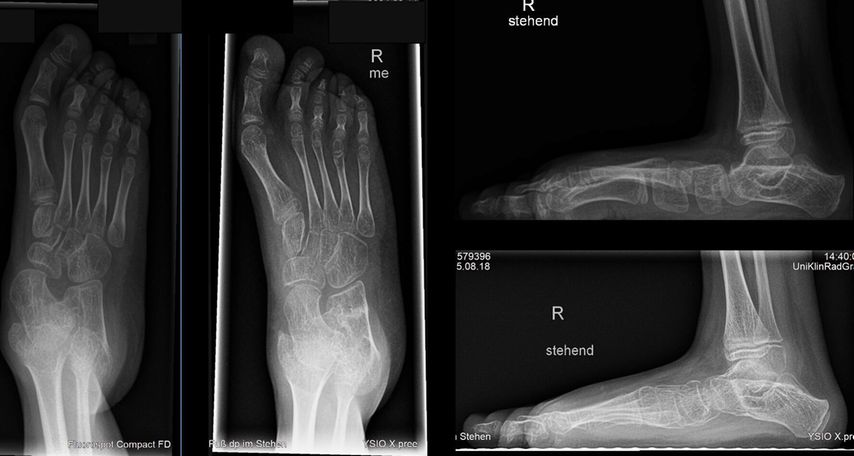

Bei einem 9-jährigen Mädchen mit angeborenem Knick-Senk-Fuß beidseits wurde ein kommerziell verfügbarer Allograft-Knochenblock zur Evans-Osteotomie erfolgreich angewendet. Im Rahmen einer ersten Operation wurde der rechte Fuß adressiert (Abb. 1) und im Verlauf ein Jahr später das gleiche Verfahren auf der Gegenseite problemlos eingesetzt. In der Verlaufskontrolle 1 Jahr postoperativ zeigen sich eine gute knöcherne Einheilung, eine adäquate Fußaufrichtung und eine Verlängerung der lateralen Säule. Das Allograft ist nativradiologisch noch abgrenzbar. Ein weiterer Fall einer komplikationslosen Evans-Osteotomie mit kommerziellem Allograft-Knochenblock ist der eines 14-jährigen Jungen mit Knick-Senk-Fuß links. Abgebildet ist die Verlaufskontrolle 6 Wochen postoperativ, wobei im Rahmen der ambulanten Kontrolle die Kirschnerdrähte nach 6 Wochen entfernt wurden. Ein Folgeröntgen ist noch ausständig (Abb. 2). Bei einer 15-jährigen Patientin mit schmerzhaftem Knick-Senk-Fuß beidseits zeigt sich ebenso eine adäquate Fußkorrektur in der Jahreskontrolle nach Evans-Osteotomie mit Allograft-Knochenblock rechts. Eine Versorgung der Gegenseite ist geplant (Abb. 3). Auch im Fall eines 11-Jährigen mit Serpentinenfüßen kamen bereits Allograft-Knochenblöcke erfolgreich zum Einsatz: Präoperativ zeigte sich hier ein Rückfußvalgus mit Vorfuß adductus und damit verkürzter lateraler Fußsäule. Als operative Sanierung wurde eine Fußkorrektur durchgeführt, die Aspekte einer modifizierten Cotton-, Evans- und Cuboid-Osteotomie enthält. In der postoperativen Röntgenaufnahme 8 Wochen später zeigte sich eine gute knöcherne Einheilung bei stabiler Korrektur, sodass die Drähte gezogen werden konnten (Abb. 4).

Abb. 3: 15-jähriges Mädchen mit Knick-Senk-Fuß, prä- und postoperative Röntgenaufnahmen 1 Jahr nach Evans-Korrektur des rechten Fußes ap und seitlich